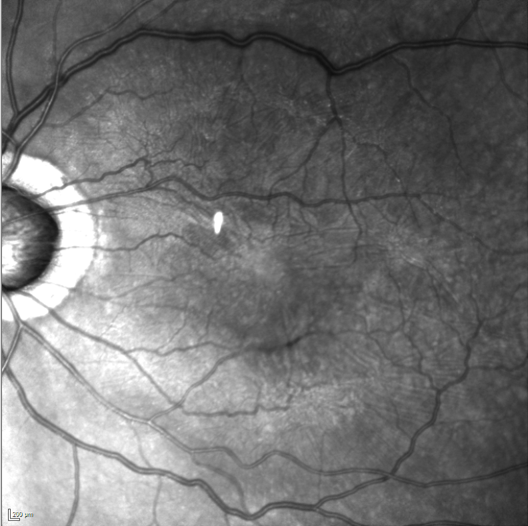

Rétinophoto couleurs d’un œil gauche, présentant une membrane épi rétinienne, plis rétiniens visibles (flèches)